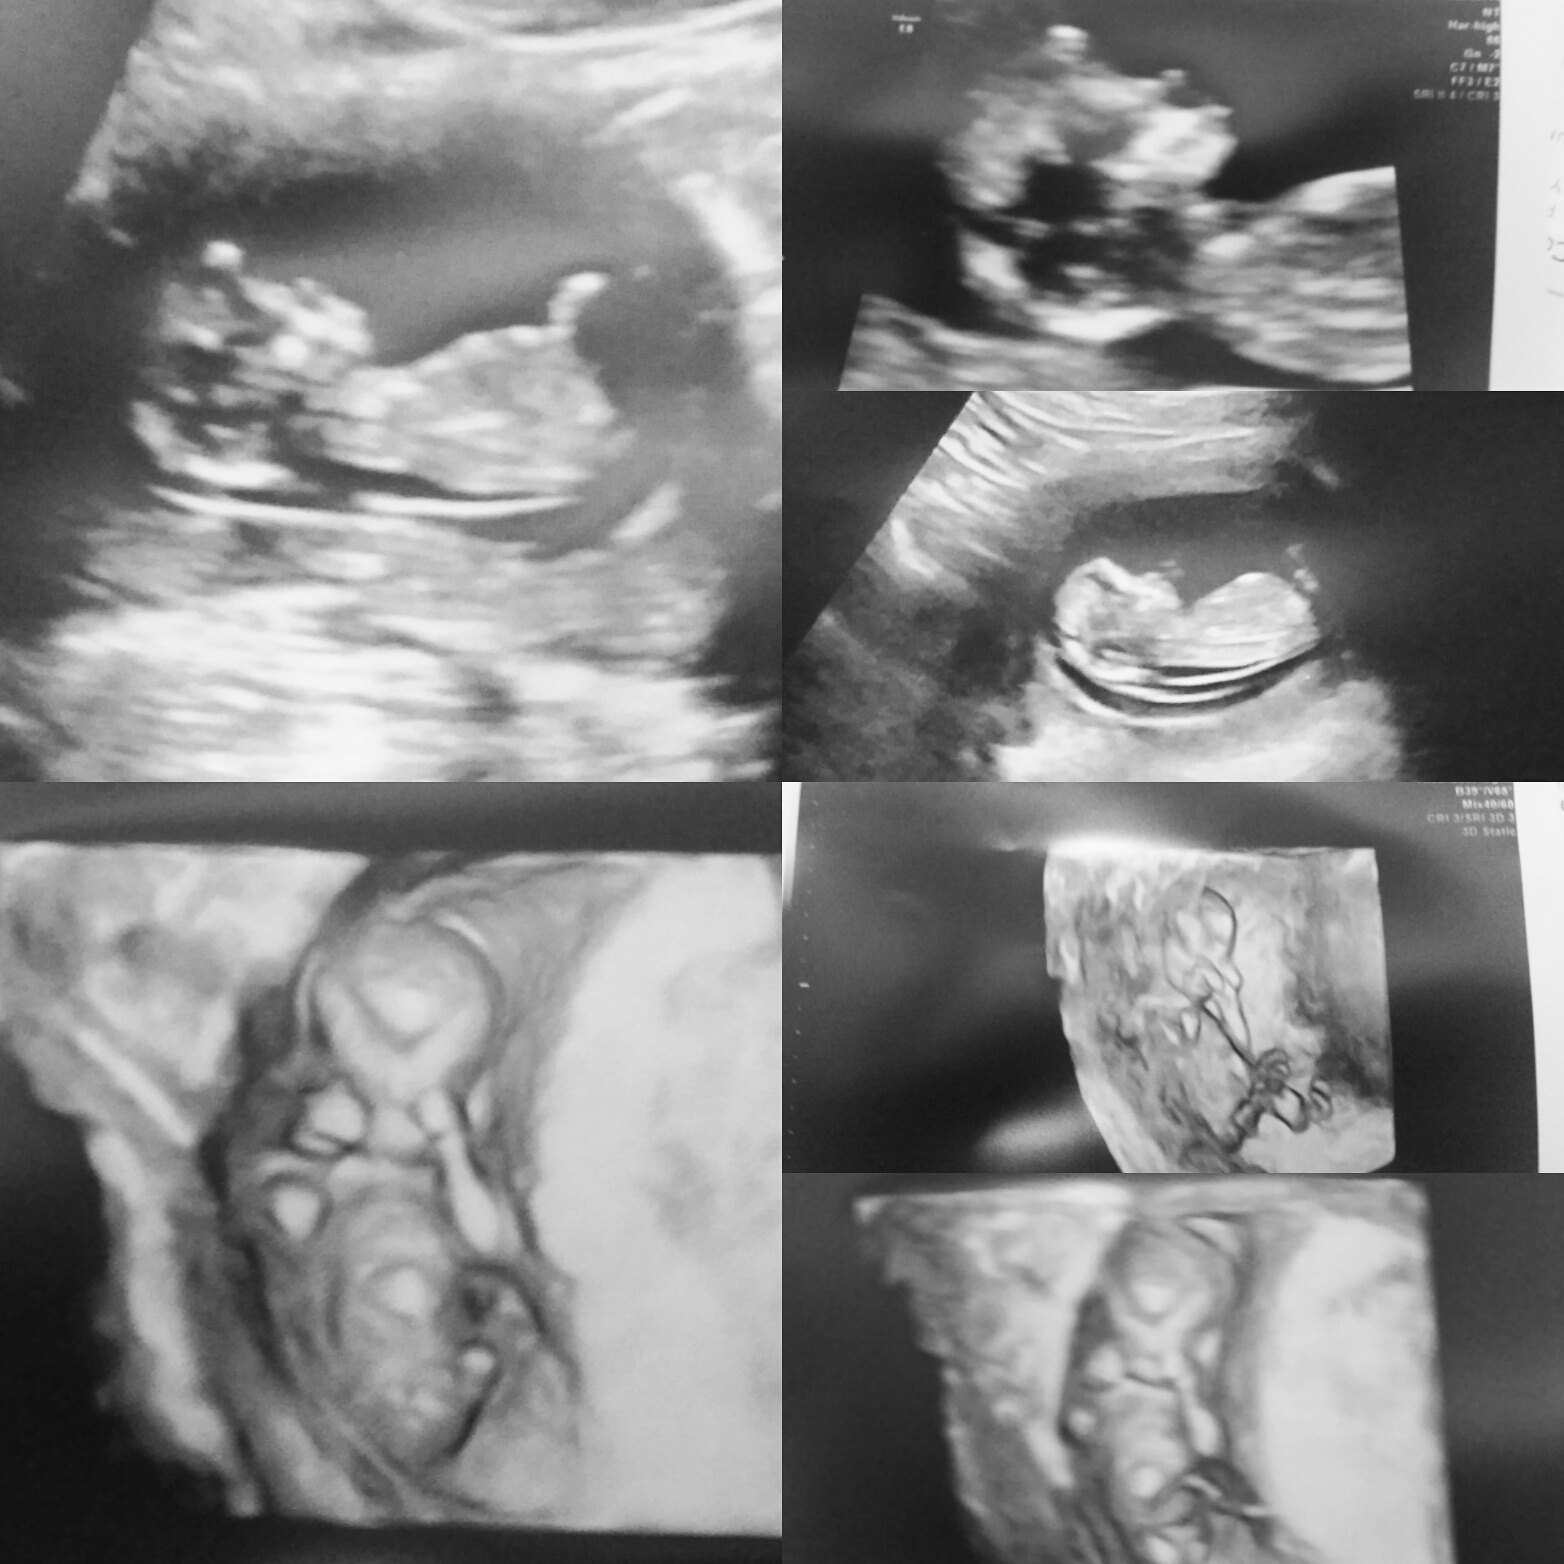

8 week ultrasound and there's twins! We were only able to see one heart beat and they thought I'm a week behind where I thought I was so please send good growing thoughts my way. Headed back in a week to hear Baby B. also if anyone has had experience in this area, please advise.</p>

One strong and growing baby. We are grateful for that❤️

Hey all! So my US went great today. The measurements all came back perfect. I did get my 1st tri screen as well and they are going to do a baseline 24hr urine just to see. All in all, great visit (even if the MFM specialist is one of my students' mom!)

@kbrands7 I missed why you had to have the ultrasound but so relieved for you things are good. But now, can we talk about those baby fingers?!?! Aghhh can't wait for my next scan, so precious!!

I love the fingers too! It was so amazing to see little one bopping around and putting fingers in his/her mouth. :x I hope you get to see some cuteness (and of course a healthy baby) during your next scan!

We had our first ultrasound yesterday, baby is measuring right on track for a due date of 5/18. I'm 10 weeks today. Strong heart beat too! Loved seeing our sweet, little one for the first time!

Finally had our ultrasound yesterday. 9 weeks exactly! HB is 163 BPM. I was so nervous walking into that room that something may have been wrong. I am so thankful and feel so blessed that our baby is healthy! :x :x

I am so happy! Had an ultrasound at 12w2d today, after losing last pregnancy in a MMC. Baby was kicking and doing really well, measuring at 12w6d! I just feel like I can finally breathe, being over the milestone of when we lost LO last time.

9 weeks 5 days. Got to see bean's heartbeat and a little movement!!! Idk what was sweeter, seeing the movement or the look on my husband's face when it happened! I'm on cloud 9 today!